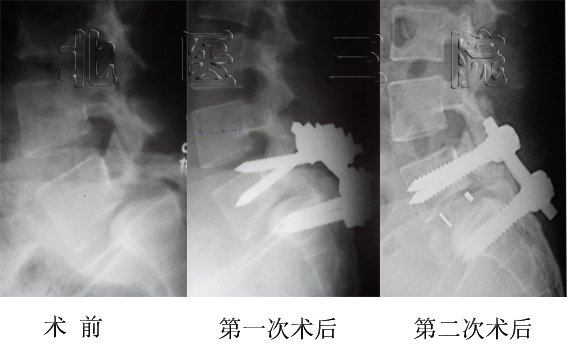

女性,14岁, L5重度发育不良性滑脱(ⅴ°),行前后联合入路L5椎切除、S1上终板截骨、L4-S1固定融合术。